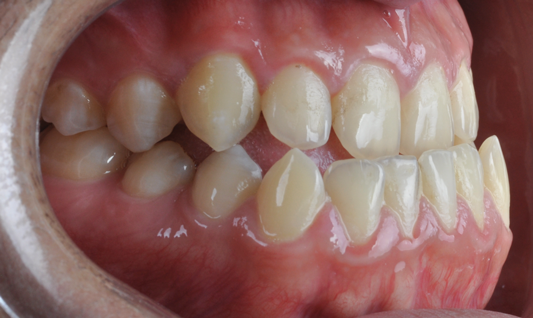

Fig 3. Pretreatment dental views of the patient; right lateral view (Fig 3), frontal view (Fig 4), and left lateral view (Fig 5).

Figure 3

Fig 13. Dental views of the patient 3 years after surgical-orthodontic correction; right lateral view (Fig 13), frontal view (Fig 14), and left lateral view (Fig 15).

Figure 13